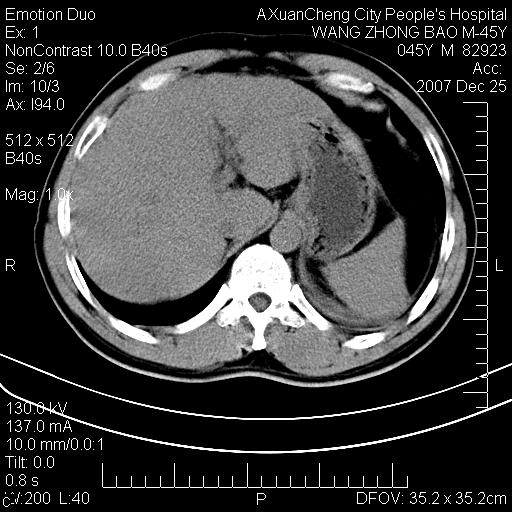

以下是引用qiuleiyu在2007-12-25 18:14:00的发言:[br]胰腺增大,周边渗出改变,肾前筋膜明显增厚,示少量积液.胆囊壁毛糙,周边少许渗出,胆总管壁厚,异常强化,然扩张不明显.结合病程急短;考虑;胆管炎,胆囊炎,胆源性胰腺炎可能大,请结合实验室检查及随访.

以下是引用lisihao在2007-12-25 14:23:00的发言:[br]急性水肿型胰腺炎[br]依据:1、胰腺弥漫性肿大,边缘稍毛糙;[br] 2、双侧肾周筋膜增厚,尤以左侧为甚(重要征象)[br] 3、双侧后胸膜增厚(刺激性炎症);[br] 4、结合病史,查血尿淀粉酶应该可以确诊。